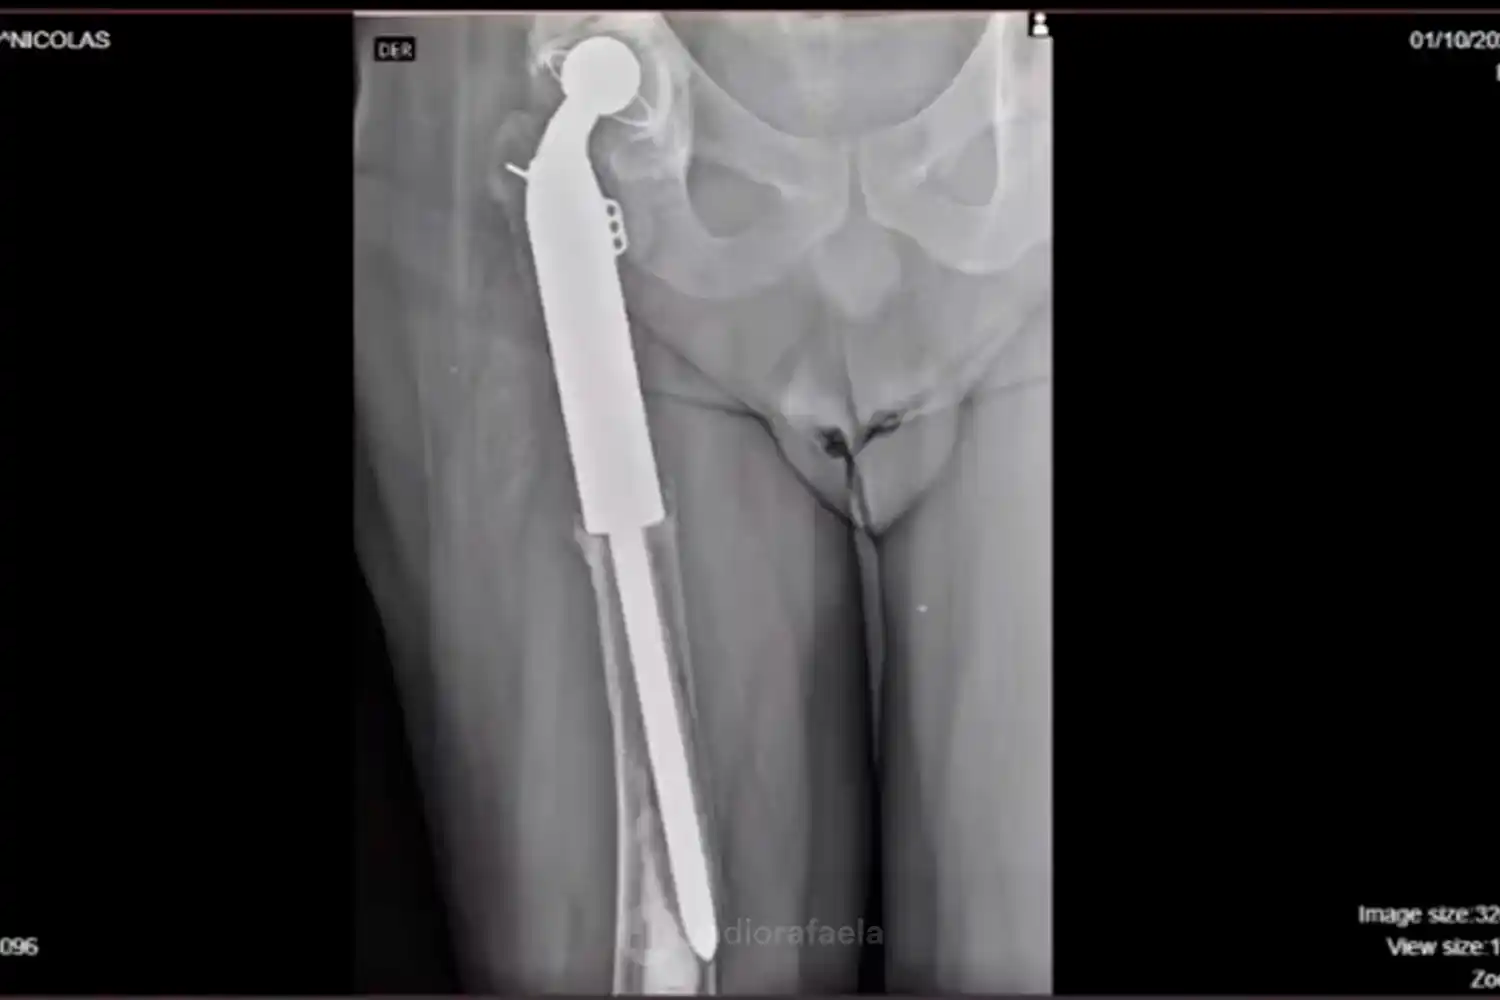

Leandro recordó que hace quince años fue diagnosticado con un cáncer de hueso. “Tuve un osteosarcoma y me tuvieron que poner una prótesis en la pierna derecha”, señaló. Tras atravesar tratamientos de quimioterapia, fue operado en Buenos Aires, donde los estudios posteriores confirmaron que la enfermedad había sido completamente removida.

“La prótesis tenía una vida útil estimada de entre veinte y veinticinco años, pero en septiembre del año pasado tuve un accidente en casa y la prótesis se desplazó”, explicó. Según indicó, “la única solución posible es un cambio completo de prótesis”.

De acuerdo al diagnóstico médico, el valor del implante asciende a una suma muy elevada. “El costo de la prótesis es de 17 mil dólares”, precisó Groj, quien remarcó que actualmente no cuenta con cobertura médica.